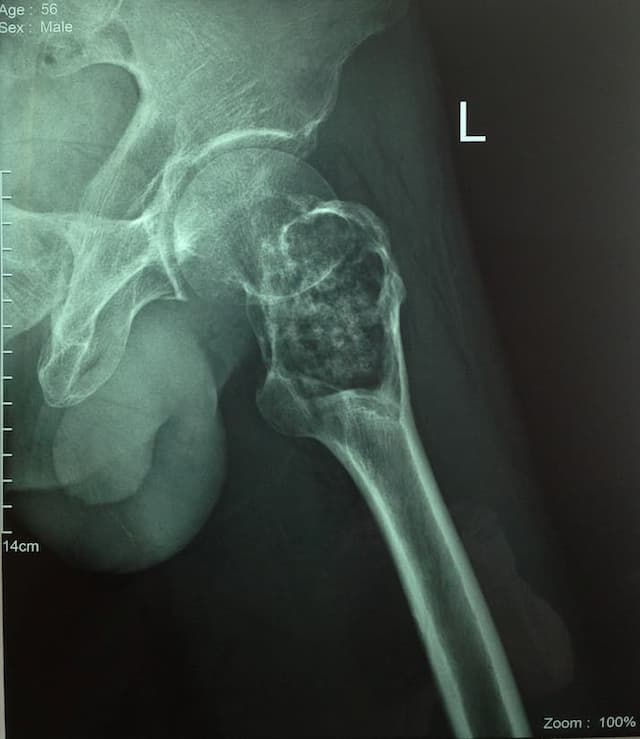

Түнхний толгой хэсгийн цусан хангамжийн алдагдалын улмаас үхжилт өөрчлөлттэй өвчтөний мэс заслын өмнөх болон дараах рентген зураг

Түнхний үе бүтэн солих мэс засал (THA) image1Түнхний үе бүтэн солих мэс засал (THA) image2